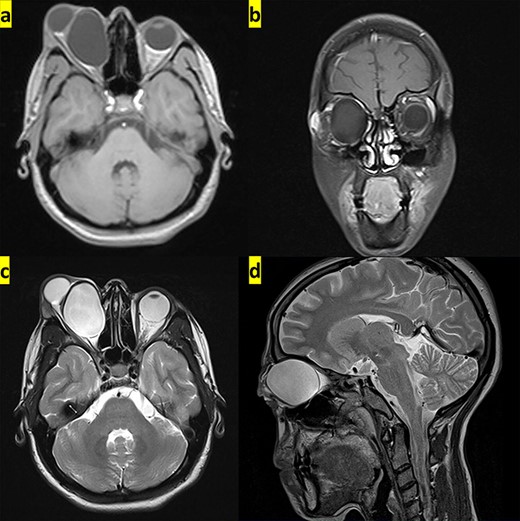

The transverse and coronal planes from MRI show hypointense hydatid cyst on T1-weighted images (a and b), whereas it appears hyperintense in the transverse and sagittal planes from MRI on T2-weighted images (c and d).

On physical examination, the patient was conscious, responsive and oriented. Visual acuity was only a perception of light in the right eye, and there was a complete restriction in this eye movement with severe chemosis (Fig. 1). The exophthalmia was non-axial, painless, non-tender, irreducible and non-pulsative. Magnetic resonance imaging (MRI) revealed a well-defined cystic lesion that measures ∼42 × 36 × 32 mm, located in the right orbital cavity displacing the optic nerve laterally. The lesion showed low signal intensity on T1-weighted images (Fig. 2a and b) and high signal intensity on T2-weighted images (Fig. 2c and d).